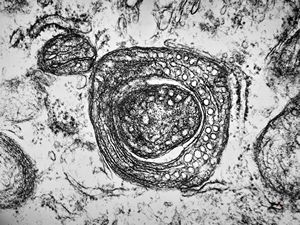

M,7m. | a formation of Birbeck granule(Langerhans granule, X-granule) - skin, histiocytosis X

M,7m. | Birbeck granules (Langerhans granules, X-granules) - skin, histiocytosis X

M,7m. | Birbeck granules (Langerhans granules, X-granules) - skin, histiocytosis X

M,1y. | Birbeck granules (X-granules) - skin, histiocytosis X

M,1y. | Birbeck granule (X-granule) - skin, histiocytosis X